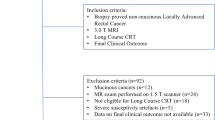

We included 39 patients (men: women, 21:18; mean age ± standard deviation, 59.1 ± 9.7 years) with mid-to-lower rectal cancer who underwent a long-course of CRT and high-resolution rectal MRIs between January 2020 and April 2021. Axial T2WI was reconstructed using the conventional method (MRIconv) and DLR with two different noise reduction factors (MRIDLR30 and MRIDLR50). The signal-to-noise ratio (SNR) of the tumor was measured. Two experienced radiologists independently made a blind assessment of the complete response on MRI. The sensitivity and specificity for pCR were analyzed using a multivariable logistic regression analysis with generalized estimating equations.